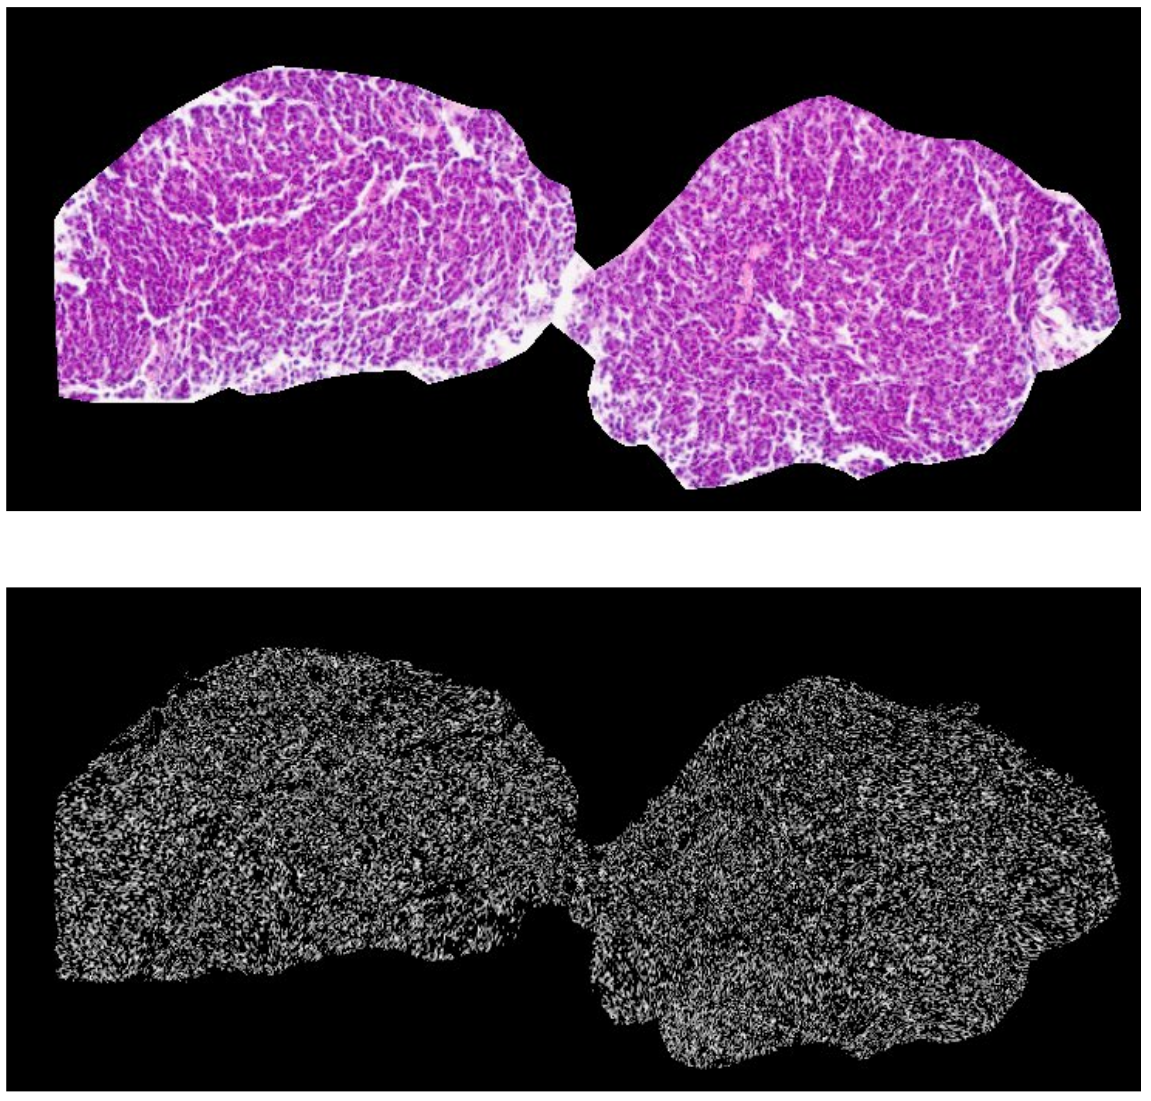

Image Processing

Multi-Modal Image Integration

Our co-registration of Hematoxylin and Eosin (H&E), Laser Ablation-Inductively Coupled Plasma-Mass Spectrometry (LA-ICP-MS), and Imaging Mass Cytometry (IMC) images provides complementary information about the cellular and molecular characteristics of cancer tissue, enabling a more comprehensive understanding of the disease.